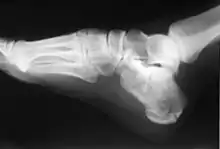

In humans and many other primates, the calcaneus (/kælˈkeɪniəs/; from the Latin calcaneus or calcaneum, meaning heel;[1] PL: calcanei or calcanea) or heel bone is a bone of the tarsus of the foot which constitutes the heel. In some other animals, it is the point of the hock.

In humans, the calcaneus is the largest of the tarsal bones and the largest bone of the foot. Its long axis is pointed forwards and laterally.[2] The talus bone, calcaneus, and navicular bone are considered the proximal row of tarsal bones.[3] In the calcaneus, several important structures can be distinguished:[3]

The calcaneus is part of two joints: the proximal intertarsal joint and the talocalcaneal joint. The point of the calcaneus is covered by the calcanean bursa.